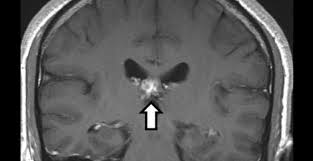

Ce Britannique de 50 ans n’aurait jamais pu imaginer que la source de ses violentes migraines et ses sensations olfactives étranges avaient pour origine la présence dans son cerveau d’un ver plat parasite d’un centimètre de long. En effet, les médecins de l’Addenbrooke’s Hospital, à Cambridge, lui ont diagnostiqué un parasite qui s’abritait depuis quatre ans dans son cerveau.

Pour ce qui est de l’invité surprise, il s’avère qu’il fait partie des Plathelminthes, une catégorie dans laquelle on retrouve des espèces de parasites comme la douve du foie ou le ver solitaire. Seulement, ce plat n’est pas très connu contrairement au ver solitaire ou encore la douve du foie.

D’ailleurs, ce Spirometra erinaceieuropei, est pour la première fois détecté au Royaume-Uni. Ainsi, il s’agit d’un cas inhabituel d’infection comme l’a précisé l’un des membres du corps médical en charge du patient. En effet, Effrossyni Gkrania-Klotas a expliqué dans un communiqué que les médecins ne s’attendaient pas à observer une telle infection au Royaume-Uni car ce genre est très rare.